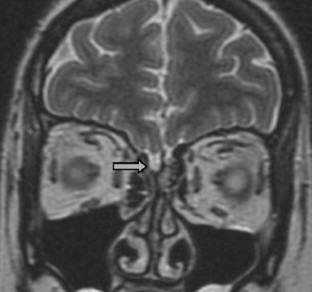

Fig. 2